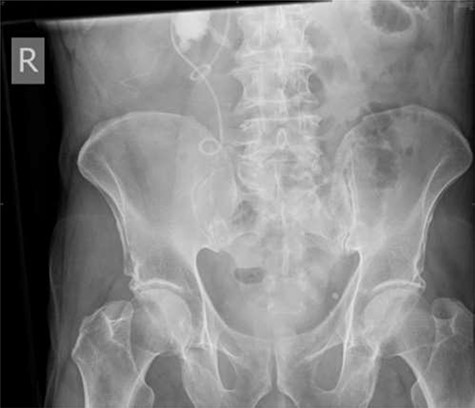

On day three post-procedure, the patient had an abdominal X-ray, which demonstrated correct positioning of the stent (Fig. 3). They were discharged from hospital on day five with planned follow-up for cystoscopic stent removal under local anaesthetic in 6 weeks.

Post-operative plain abdominal X-ray demonstrating acceptable right ureteric stent position.